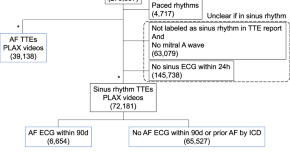

Deep learning evaluation of echocardiograms to identify occult atrial fibrillation

- Nathan R. Stein

- David Ouyang